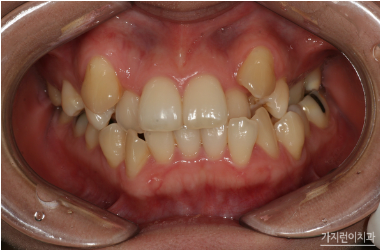

안녕하세요? 옛날에는 송곳니가 덧니로 난 게 귀여움의 상징이었지만 최근들어서는 가지런한 치열이 미덕으로 보이고 있습니다. 좀 더 신뢰감도 주고 장난끼를 빼기 때문에 정직한 이미지까지 생겨나는데요. 그래서 덧니가 송곳니로 난 사람들은 강남치아교정을 알아보기도 합니다. 그렇다면 덧니는 왜 송곳니에만 나는 걸까요? 덧니는 영구치가 날 자리가 부족할 경우에 생겨나게 됩니다. 턱뼈의 크기는 작고 치아의 크기가 상대적으로 크다면 생겨나기 쉽겠죠.

덧니는 특히 송곳니가 많은 편인데요. 송곳니의 특성상 나중에 나는 펀이기 때문에 잘못된 방향으로 맹출하게 되면 송곳니가 덧니로 자라나게 되는 것입니다. 즉 송곳니 뿐만 아니라 앞니에도 덧니가 생길 수 있다는 소리죠. 덧니치아교정은 치아가 포개져 있는 부분의 관리를 위해 시도하는 게 좋은데요. 충치나 잇몸질환에 쉽게 노출될 수 있는 환경이기 때문에 1급 부정교합으로 분류하고 있습니다. 가급적 빠른 치아교정을 통해 정돈된 치열로 건강을 챙겨보는 게 좋겠습니다.